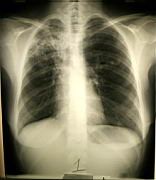

TB in the right upper lobe |